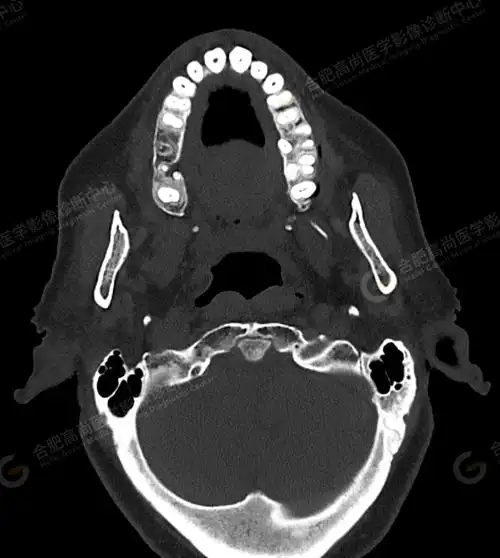

【高尚病例】术前检查头颅ct平扫发现"颅底凹陷症"1例_测量_枕骨_显示